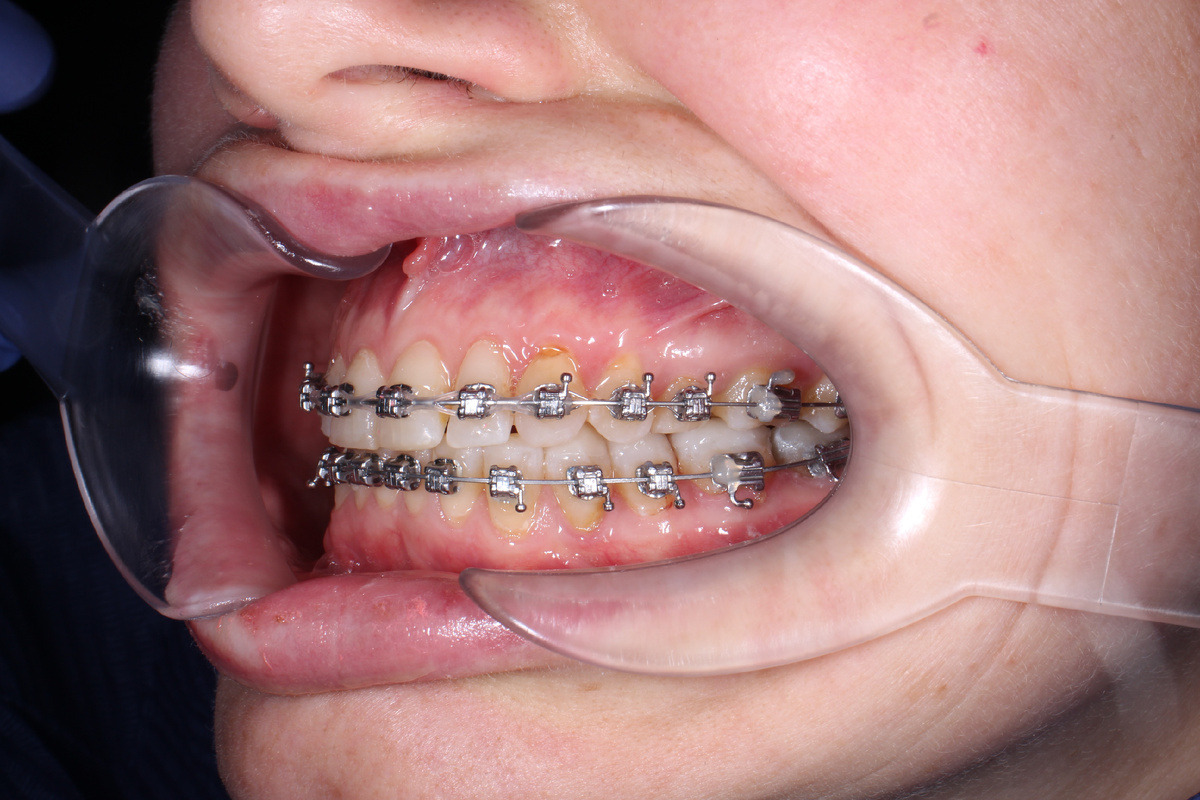

Главная задача накладок — это так называемая дизокклюзия, или, проще говоря разобщение прикуса. Зачастую, особенно в случаях глубоко прикуса если просто наклеить брекеты на нижние зубы сразу, то при смыкании челюстей ваши верхние зубы просто «собьют» нижние замочки. А если брекет выстоит под напором жевательного давления, то длительный контакт зуба с брекетом, особенно керамическим, приведёт к стираемости зуба. Оба варианта негативно сказываются на результате ортодонтического лечения.

Накладки создают временную «опору», которая не дает до конца сомкнуть зубы тем самым предотвращая контакт между брекетом и зубом, значительно снижая риск отклейки замочка.

Самые известные и заметные — это те самые «синие пломбы» на жевательных зубах. Почему синие? Все просто: чтобы врач легко мог отличить их от зуба, когда придет время их снимать, т.к. такие накладки временные.

Бывают и передние накладки, которые ставятся на небную поверхность передних резцов. Они выглядят как маленькие площадки или ступеньки, в которые упираются нижние резцы. Такие накладки используются для лечения глубокого прикуса, когда нам нужно, чтобы задние зубы «прорезались» чуть выше и подняли высоту лица.